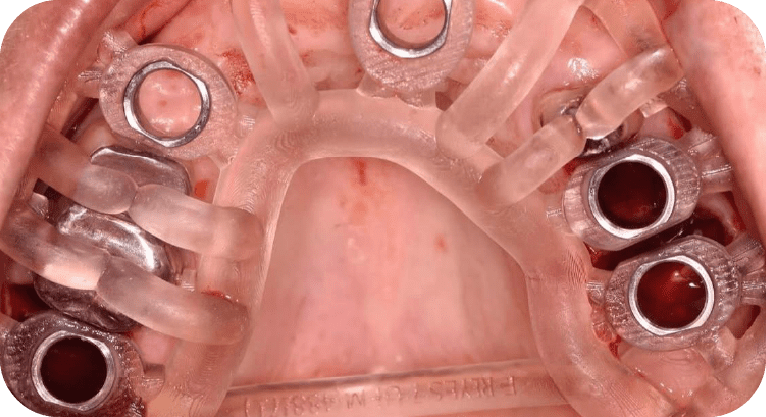

Female patient, “52” years old

Treatment: All-on-4

The patient came to the clinic aer losing several upper teeth due to cavities and was using a removable denture that she founduncomfortable. She wanted a fixed solution, so a full rehabilitation was performed using the All-on-4 technique, placing 4 dental implants that support a fixed prosthesis. This restored her functionality, confidence, and a natural-looking smile permanently.